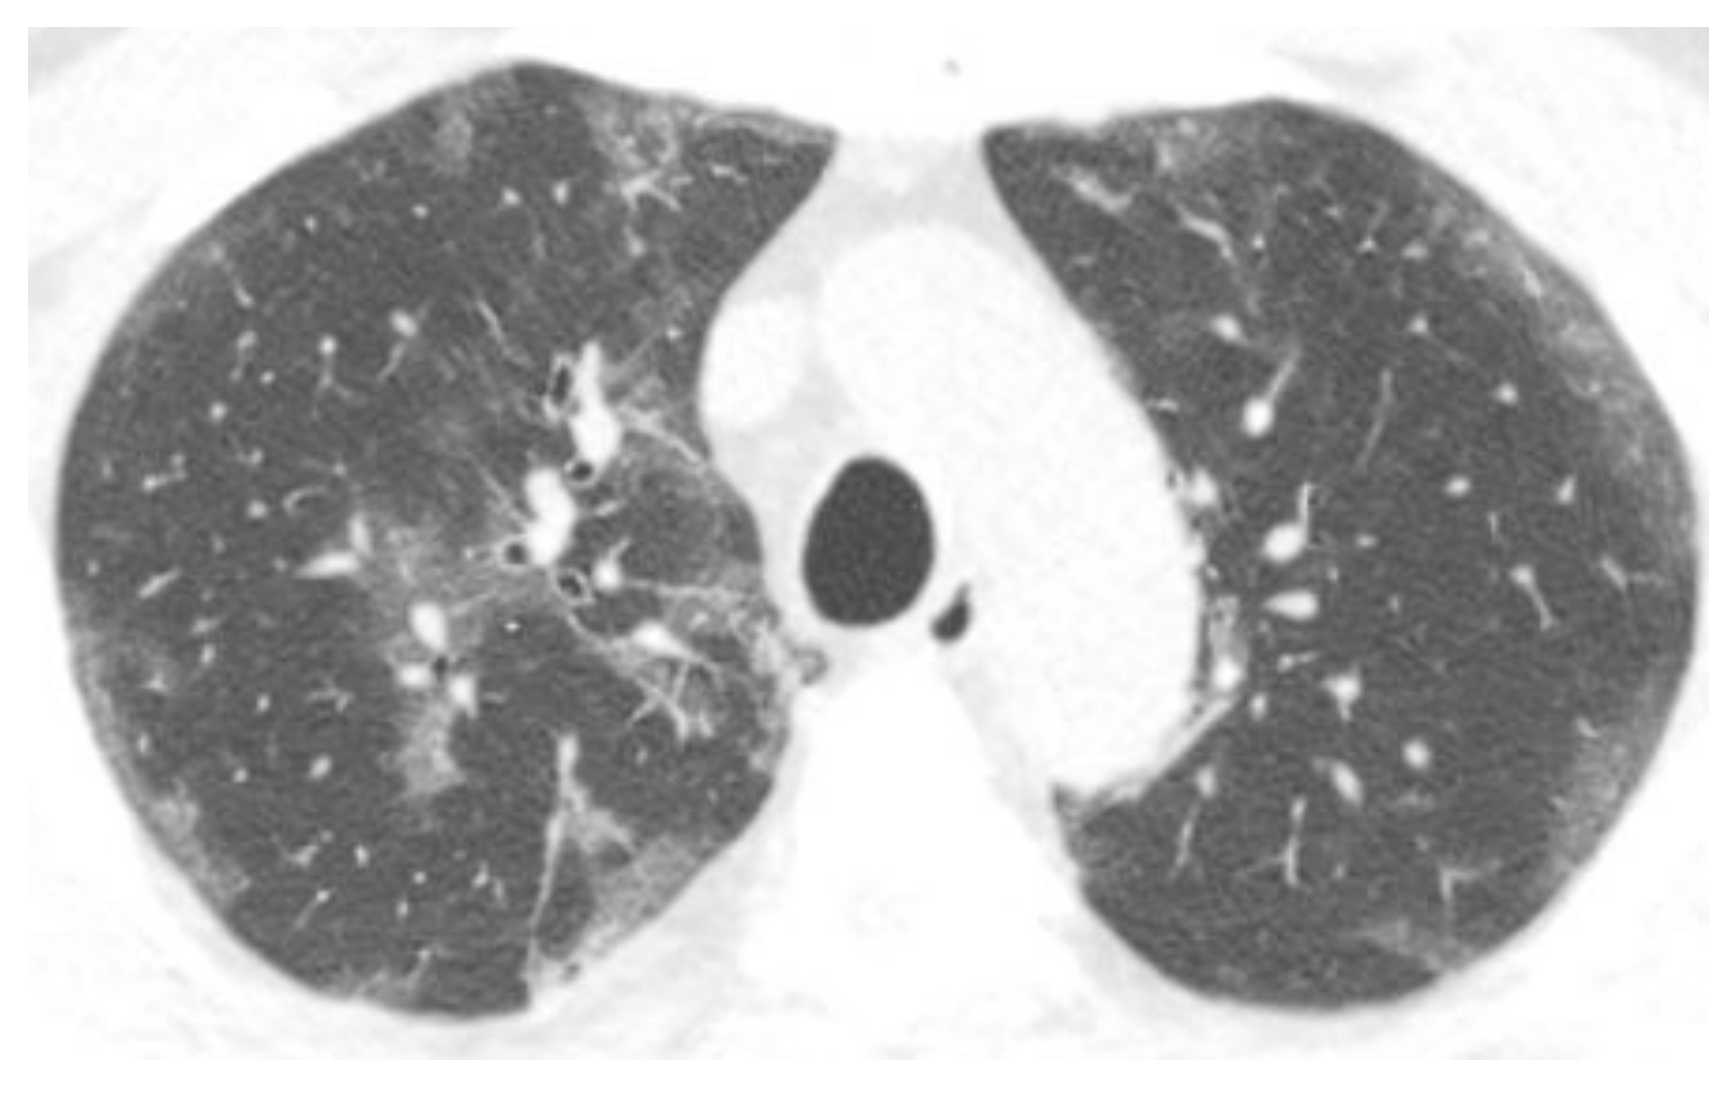

4.2. Epithelial Dysfunction